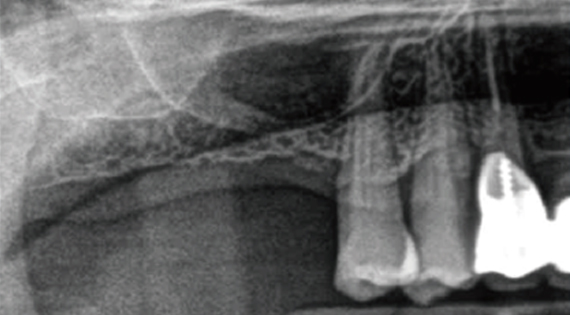

In the case of bone graft case(maxillary sinus), the operator can directly grasp the maxillary sinus membrane and adjust it so that the maxillary sinus membrane can be elevated in the desired direction and the implant can be placed after bone transplantation in the maxillary sinus.

As the amount of bone removal increases due to the 2 stage surgery, bone damage, pain and swelling are large.

2. Forming Window in the bone

3. Elevating window & sinus membrane

4. Placing bone grafting material